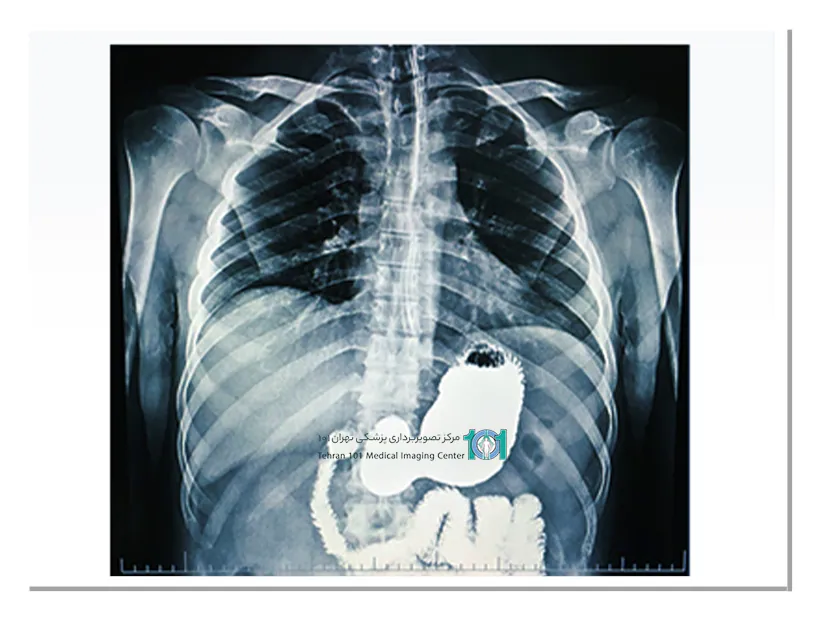

پرتونگاری معده یک روش تصویربرداری پزشکی است که با استفاده از اشعهی ایکس، تصاویری دقیق از معده و سیستم گوارشی بدن ایجاد میکند. این روش معمولاً برای تشخیص بیماریهای معده، مانند زخم معده، التهاب معده، تورمها و تودههای خطرناک استفاده میشود. این آزمایش به پزشک شما کمک میکند تا ناهنجاریهای عملکردی و ساختاری را پیدا کند.

پرتونگاری معده (UGI) یک آزمایش تصویربرداری استاندارد اشعهی ایکس است که از نوع پیشرفتهِ آن به نام فلوروسکوپی استفاده میکند. اشعهی ایکس فلوروسکوپی مانند اشعهی ایکس معمولی است با این تفاوت که متحرک است. در این روش ، اشعهی ایکس متحرک تولید میشود که عملکرد اندامهای شما را نشان میدهد. این آزمایش به پزشک امکان دیدن جزئیات بصری بیشتری نسبت به اشعهی ایکس معمولی میدهد.

پرتونگاری معده چگونه انجام میشود؟

پس از پوشیدن لباس مخصوص، شما را به اتاق معاینه هدایت میکنند، که دارای یک میز اشعهی ایکس کج است که میتوانید روی آن بایستید یا دراز بکشید. سپس به شما یک محلول داده میشود که احتمالا باریم به همراه دی اکسید کربن خواهد بود.

محلول طعمدار و شیرین شده است اما باز هم ممکن است طعم خوشایندی نداشته باشد. در طول آزمایش، بسته به شرایط، محلول را به مرور و به صورت جرعهجرعه مینوشید. رادیولوژیست تصویربرداری را از زوایای مختلفی انجام میدهد؛ به همین دلیل ممکن است از شما بخواهد به روشهای مختلف حرکت کنید تا با حرکت باریم تصویربرداری از تمام نواحی انجام شود.

پرتونگاری معده آزمایشی بدون درد و غیرتهاجمی است که به پزشک شما امکان بررسی مری، معده و ابتدای رودهی شما را میدهد. فلوروسکوپی به رادیولوژیست این امکان را میدهد که اندامهای شما را در حال حرکت ببینند و نحوهی عملکرد آنها را مشاهده کنند.

علاوه بر این میتواند ناهنجاریهای ساختاری یا عملکردی را نیز نشان دهد. پزشک شما از نتایج این آزمایش برای تشخیص علائم غیرقابل توضیح شما استفاده میکند. بسته به شرایط شما پرتونگاری معده ممکن است در بیمارستان یا مراکز تخصصی انجام شود.